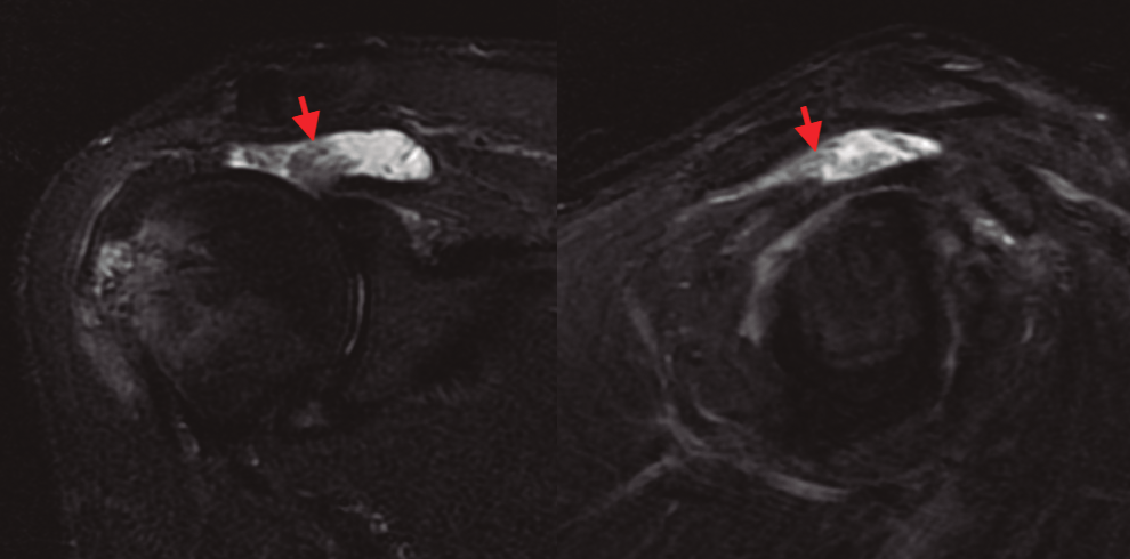

Figura 1. Imágenes en corte coronal y sagital de la ventana STIR de la RM, evidenciando rotura masiva del manguito rotador y la presencia de unas vellosidades grasas hipointensas en el seno de la bursa subacromial (señaladas mediante flechas).

En la resonancia magnética (RM) de los hombros, los citados cambios degenerativos con ­quistes subcondrales en la cabeza humeral y presencia de cambios inflamatorios en cabeza y troquíter eran evidentes, observándose el LA como una infiltración grasa con vellosidades en la cavidad articular hiperintensas en T1 y T2, con imágenes hipointensas en las ventanas STIR y supresión grasa. También se observó el acúmulo de líquido en la zona de la bursa subacromial (Figura 1), presentando en ocasiones una discreta migración proximal de la cabeza humeral. En ocasiones se evidenció también una alteración de la señal en los tendones del manguito rotador, compatibles en algún caso con roturas. En la RM de los casos de rodilla se evidenció el LA como un crecimiento de partes blandas en la bursa suprapatelar de intensidad compatible con la grasa, asociada a la presencia de derrame articular (Figura 2). Dicha masa era heterogénea, irregular, adherida al plano anterior.